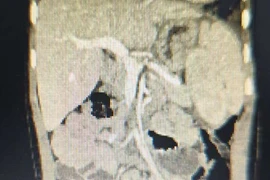

Rò khe mang là dị tật bẩm sinh vùng cổ bên được chỉ định điều trị phẫu thuật để lấy bỏ toàn bộ đường rò. Việc phẫu thuật cần thực hiện tại cơ sở y tế có đầy đủ trang thiết bị để hạn chế biến chứng nguy hiểm.